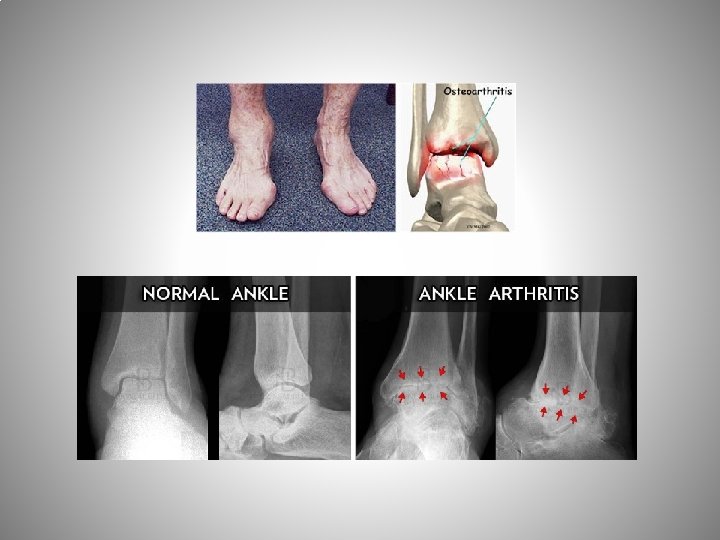

Ayak Bilek OA Ayak bileğinde en sık dejeneratif artrit Sekonder OA en sık (post travmatik) Primer OA seyri yavaş, post travmatik değişken • Erişkinlerde % 1 -4 ayak bilek OA (kalça & diz) Koksartroz ve gonartroza göre genç yaş Yük taşıyan majör eklem & nispeten küçük bir eklem yüzeyi ve yüksek temas alanları yüklenmesine rağmen NADİR İyi tasarlanmış bir menteşe eklem olmasına bağlı biyomekanik özellik & kıkırdak yapısından

Ayak Bileği OA Etkisi (IMPACT) Eklem ağrısı , ROM kaybı, fonksiyonel kısıtlanma • Ağrı, yaşam kalitesinde düşme ve fonksiyonel kısıtlanma parametrelerine göre Koksartroz End-stage böbrek Konjestif kalp yetmezliği Radikülopati AYRICA ÇOKLUKLA GENÇ HASTA Saltzman